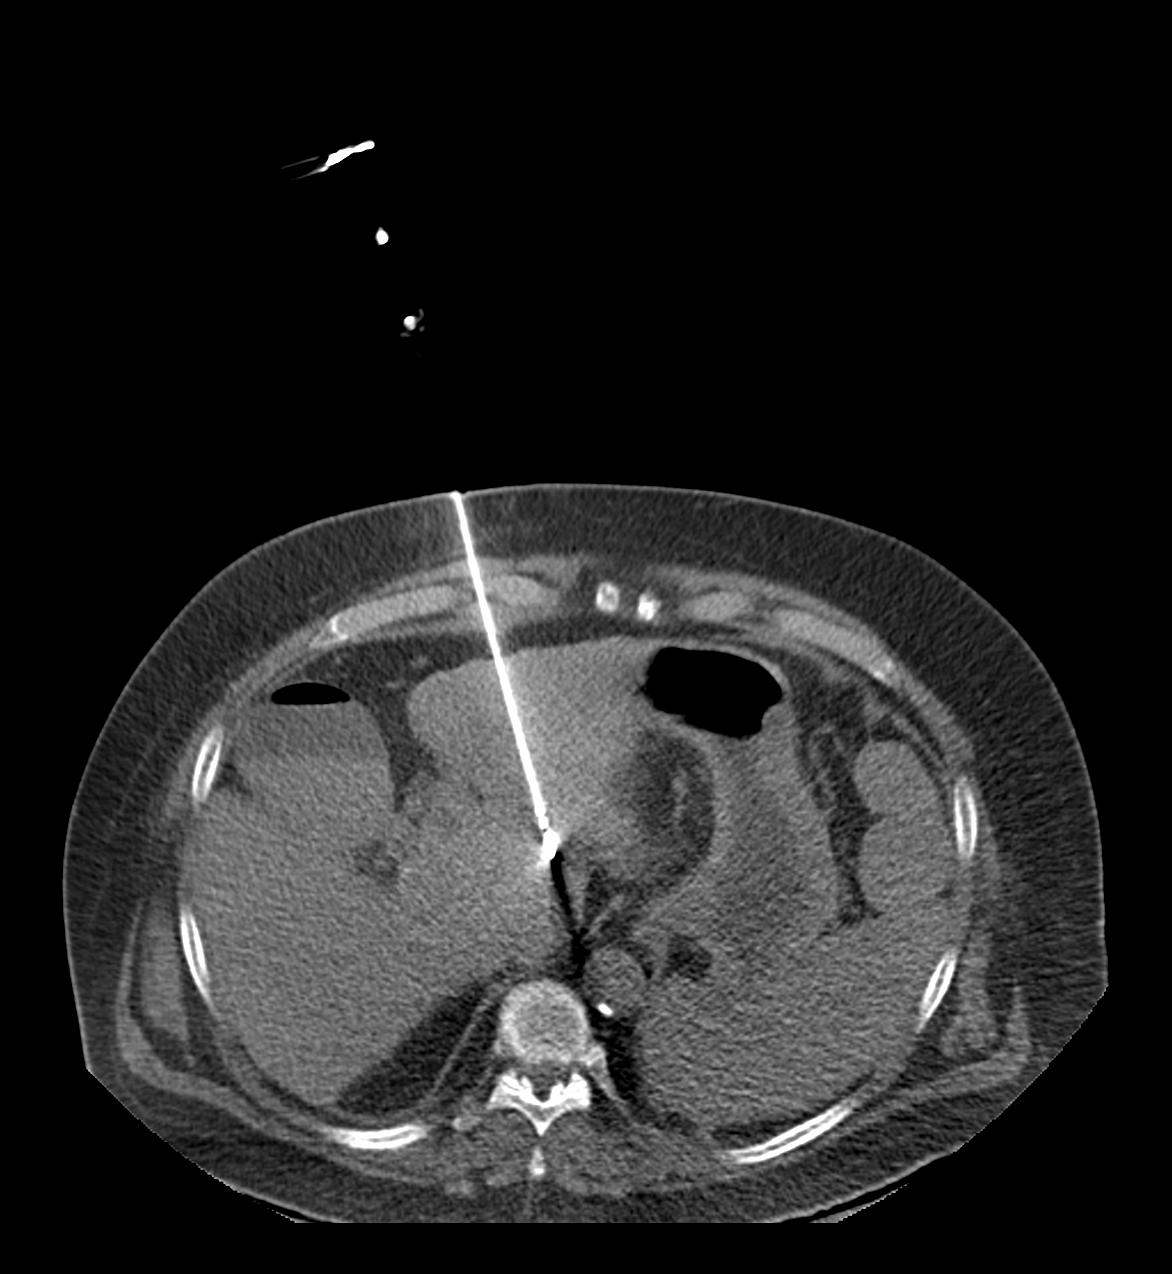

Die Entscheidung, ob bei Ihnen eine Gewebeprobe entnommen bzw. eine Drainage angelegt wird, entscheidet sich prinzipiell erst nach der Durchführung einer diagnostischen CT oder MRT des betreffenden Organs. Wenn die diagnostische Untersuchung an anderer Stelle durchgeführt wird bzw. wurde, müssen Sie die Bilder der Voruntersuchung bitte bei uns abgeben, damit die Intervention geplant werden kann. Für die Punktion benötigen wir aktuelle Laborwerte für die Blutgerinnung (Quick, INR, PTT). Unter Umständen ist es auch im Rahmen des Eingriffs erforderlich, dass Kontrastmittel verabreicht wird. Für alle Eingriffe müssen Sie am Untersuchungstag nüchtern sein. So früh wie möglich, spätestens am Tag vor dem Eingriff findet ein Arztgespräch statt. Falls Sie noch offene Fragen zur Untersuchung haben, werden diese vom Arzt beantwortet.

Die Dauer eines CT gestützten Eingriffs richtet sich nach dem zu punktierenden Organ und dauert ca. 30 Minuten. In der Regel werden Sie eine örtliche Betäubung erhalten und evtl. zusätzlich mit schmerzstillenden und/oder sedierenden Medikamenten vorbehandelt werden. Solche Eingriffe werden meist unter stationären Bedingungen vorgenommen, um Sie ausreichend nachbeobachten zu können. Bei ambulanten Eingriffen werden Sie nach dem Eingriff mindestens vier Stunden überwacht werden, bevor Sie nach Hause dürfen. In solchem Fall empfehlen wir dringend, nicht selbst ein Fahrzeug zu führen, weil Sie möglicherweise durch den Eingriff selbst oder die dabei verabfolgten Medikamente in Ihrer Fahrtüchtigkeit eingeschränkt sind.

In der Klinik für Diagnostische und Interventionelle Radiologie und Nuklearmedizin wird die lokale perkutane Tumorablation durch Radiofrequenzablation oder Mikrowellenablation durchgeführt. Dabei handelt es sich um Verfahren, bei denen in einem vorher definierten Bereich des Körpers Gewebe durch die Zufuhr von großer Hitze zerstört wird. Klassischstes Beispiel ist die lokale Zerstörung einer bösartigen Raumforderung. In den erwünschten Zielgebieten entstehen sog. Hitzenekrosen oder Koagulationsnekrosen. Antrieb für die starke Hitzeentwicklung ist eine Form von Hochfrequenzstrom bzw. ein Mikrowellengenerator, ähnlich dem Verfahren wie es heute auch beim Veröden von Gefäßen im Rahmen von Operationen genutzt wird. Oberstes Ziel ist es, eine möglichst große Koagulationsnekrose zu erzeugen, ohne dabei dem restlichen Organismus in irgendeiner Weise zu schaden. Wir verwenden für die Radiofrequenzablation bei uns ein System mit sehr dünnen Aufspreizelektroden und einem leistungsstarken 460 Kilohertz-Generator (Video). Bei diesem technischen Verfahren erreicht man Spitzenleistungen von 250 Watt. Der Mikrowellenablator stimuliert Wassermoleküle. Dabei entsteht kinetische Reibung und Hitze, die das Gewebe verkocht. Verschiedene Wellenlängen erzeugen einen unterschiedlichen Wirkungsradius und damit auch einen unterschiedlichen Hitzeradius.

Etwa 2,5 cm bis 3,5 cm große Gewebsbereiche lassen sich pro Elektrodenposition mit beiden Varianten zerstören. Nach etwa einer Viertelstunde ist das Gewebe im Bereich der eingebrachten Ablationssonde vollständig zerstört. Während einer Ablation wird mit Hilfe einer computertomographischen Untersuchung stets die Lage der Sonde kontrolliert, um eine Zerstörung von gesundem Gewebe zu vermeiden.